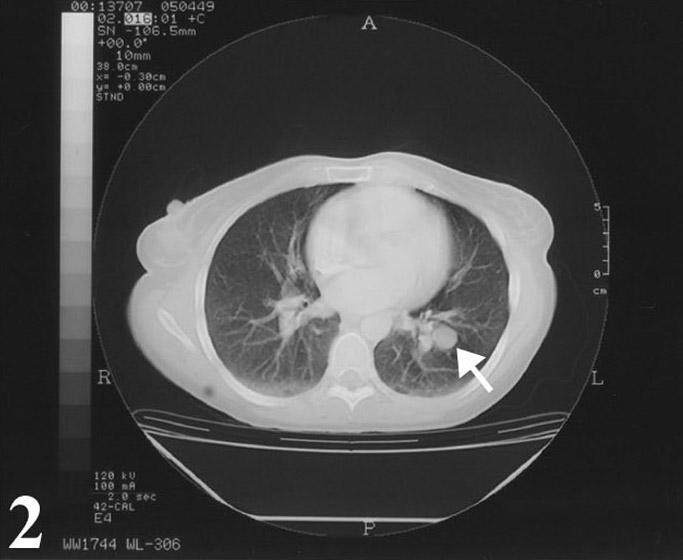

A 32-year-old Caucasian woman who was in her usual state of health until approximately 2 months ago was admitted for her new onset of chest pain and shortness of breath. She had a longstanding history of smoking since the age of 9, roughly 2–3 packs per day. Physical examination was within normal limits; no evidence of peripheral adenopathy or cutaneous nodules was noted. A chest x-ray and CT scan revealed a solitary pulmonary mass (Fig. 1, 2). The mass was round and smooth, 2.8 cm in diameter, and centrally located within the left lower lobe.